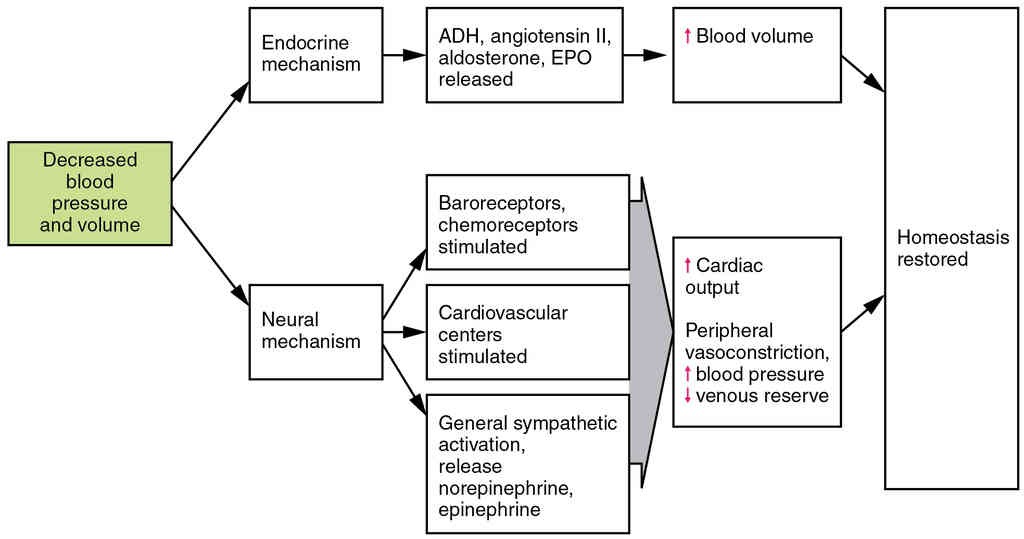

This page is under construction. For now, it is just a resource of the images found in the OpenStax Anatomy and Physiology Handbook. It wil slowly change into a revision tool. Each slide has a number. Use this to refer to the slide. When completed, it will have an unlabelled section, with labelled slides in parallel. On the unlabelled slides, write your answer and use the labelled slide to assess yourself. Keep track by also noting the number on each slide. Improvement at each attempt is important, more so than full marks on a first attempt.